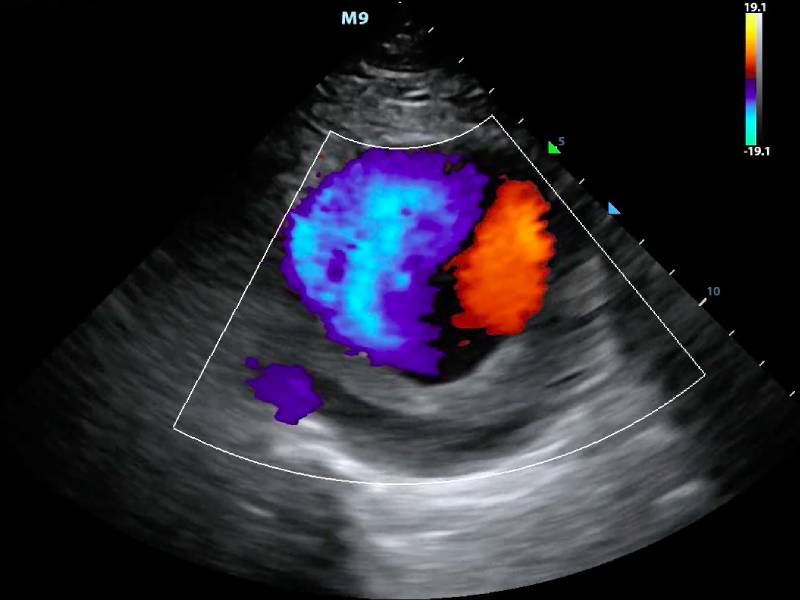

The Colour Doppler scan, a non-invasive imaging technique, provides detailed insights into blood flow and vascular structures. For Sanya, it was a beacon of hope to uncover the root cause of her discomfort. The scan was scheduled at a reputable imaging center in the heart of Karond, renowned for its advanced technology and skilled technicians.

Throughout the procedure, Arjun’s calm demeanor and thorough explanations reassured Sanya. She realized that the Colour Doppler scan was not just about diagnosing a problem—it was about empowering her with knowledge about her own body. The scan revealed an arterial blockage, a condition that, if left untreated, could have serious implications. Armed with this information, Dr. Mehta devised a treatment plan tailored specifically for Sanya’s condition.